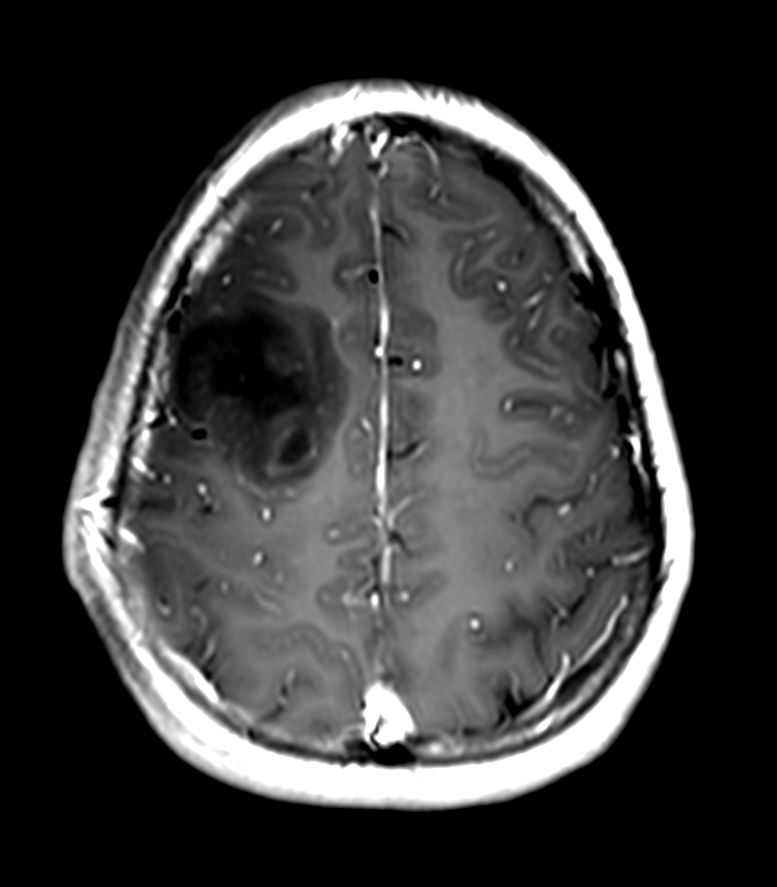

Patient with a brain lesion. ExamCard includes MultiVane XD for motion-free imaging in short scan time, Compressed SENSE to shorten exam time, SWIp to enhance contrast for deoxygenated (venous) blood or calcium deposits, a high resolution 3D FLAIR sequence enabling reformats in any plane without loss of resolution, diffusion to achieve high contrast between background and lesions, pCASL to visualize brain perfusion and functional physiology in a non-contrast manner, dynamic multi-slice T2* perfusion for quantitative analysis, and spectroscopy for a non-invasive measurement of biochemical changes in the brain.

3D T2w FLAIR - Axial Reformat Compressed SENSE